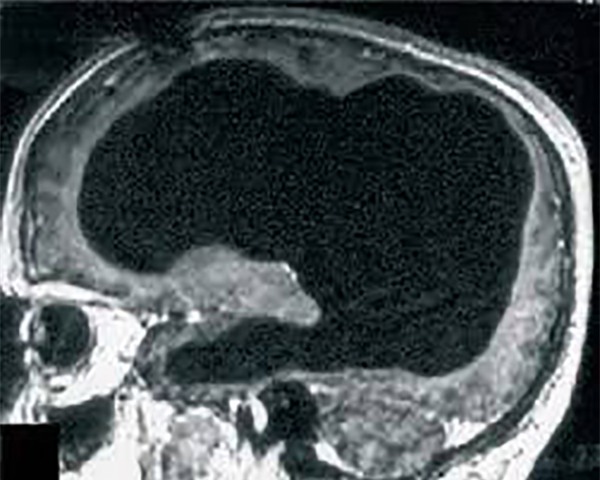

Hình ảnh chụp não của người đàn ông kỳ lạ với phần não nhỏ đến độ gần như không có.

Không những thế, ông còn lập gia đình và hai con. Ông nhập viện vì cảm thấy chân trái bị yếu nhưng sau khi chụp CT và MRI, bác sĩ thấy não thất của ông nở rộng, trong khi não, tức chất xám và chất trắng, thì lại chẳng thấy đâu.